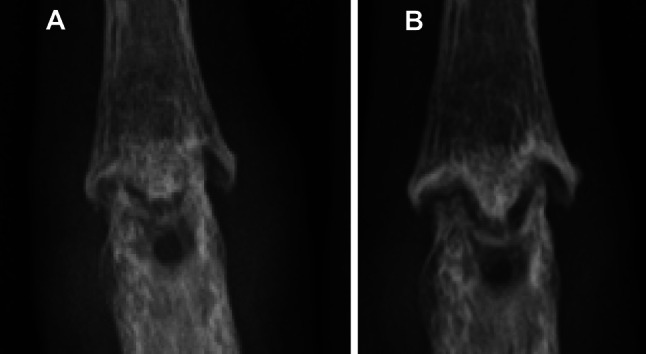

In clinical trials, molecular-targeted agents have been shown to lead to a significant reduction in symptoms and provide pain relief for patients with active RA compared with placebo or MTX alone [6–8, 10, 12, 14–17]. Especially the combination therapy with MTX yielded superior clinical efficacy to monotherapy [5–8, 10–12, 14–19]. The efficacy of some molecular-targeted agents was similar to the efficacy of MTX in the monotherapy setting [14]. Furthermore, these agents are expected to inhibit radiographic progression across all disease activity conditions, whereas joint damage has been shown to progress in patients with low and moderate disease activity levels treated with csDMARDs such as MTX [20]. Even in patients who did not show clinical improvement as evaluated by American College of Rheumatology criteria [21], combination therapy with IFX and MTX provided significant inhibition of structural damage compared with inhibition in patients who received MTX alone [22]. There might be uncoupling of inflammation and joint destruction in RA. Here, the author provided roentgenograms of a case. A 52-year-old female suffering from active rheumatoid arthritis had been treated with IFX and MTX since October 2008. Although she did not show an adequate response to IFX therapy without improvement of DAS, dramatic repair of the proximal interphalangeal (PIP) joint of her right middle finger was observed in May 2009 (Fig. 2a, b).

Fig. 2.

A case showing radiological repair despite inadequate response to a tumor necrosis factor-α inhibitor. A 52-year-old female suffering from active rheumatoid arthritis had been treated with IFX and MTX since October 2008. Although she did not show an adequate response to IFX therapy without improvement of disease activity, dramatic repair of the proximal interphalangeal (PIP) joint of her right middle finger was observed in May 2009. Roentgenogram of the PIP joints of the right middle finger in October 2008 (a) and May 2009 (b). IFX infliximab, MTX methotrexate